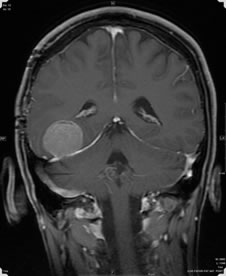

A 36-year-old man with no past medical history presented with seizures and headaches in 2004. He was found to have a right middle fossa tumor, for which he underwent two resections in 2006, with conflicting pathology reports. At that time, adjunctive therapy was advised, but the patient did not follow through. He re-presented with seizures, with recurrent tumor discovered on imaging. The neurological examination was intact, expect for right partial cranial fourth nerve palsy and right V1 to V3 numbness, which had been longstanding. The patient then had a right temporal craniotomy for resection of tumor. At surgery, the tumor was well defined and appeared to take origin from the inferior dura and the tentorium. All obvious tumor was removed, and the patient had an uneventful postoperative course. His neurological examination has been stable, and on postoperative MRI, there is no definitive residual tumor. The patient was discharged home in stable condition.